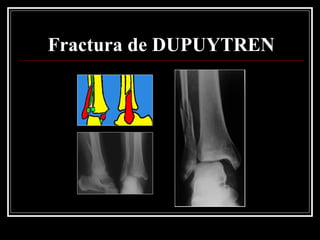

Fractura de DUPUYTREN

Tx Fractura de DUPUYTREN